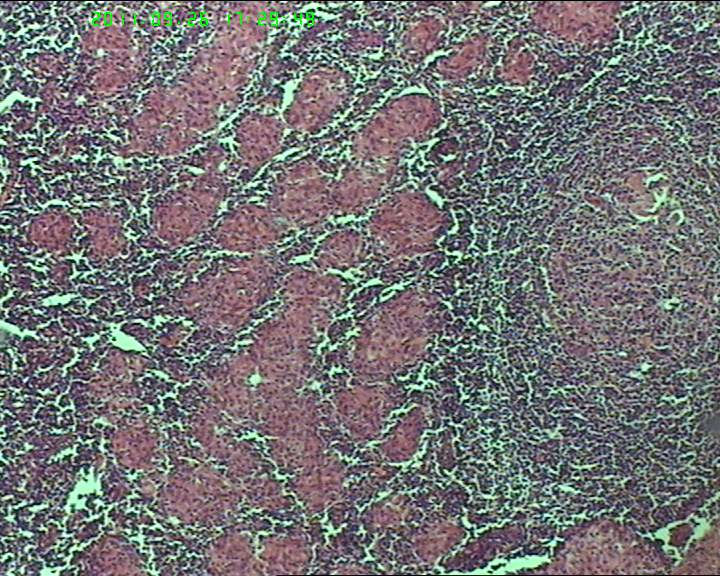

21岁女性左侧颌下淋巴结,该诊断什么?

灰白不整形肿物一个,大小3.5*2.5*2cm,包膜完整。

慢性肉芽肿性炎症,形态学倾向结节病,但是作为病理工作者对于这样的病例,再结合咋们国情,还是建议临床除外增殖性结核后再考虑结节病。

肉芽肿性炎症,倾向结节病。

最好做做抗酸染色、网状纤维染色和PAS后看看再定。